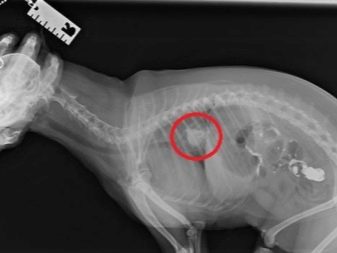

• It happens that small fragments of bones are collected in the stomach into a dense conglomerate, which cannot be released naturally from the dog. A cleansing enema, oil rectal suppositories, and in more complex cases, surgical intervention will help alleviate the condition.